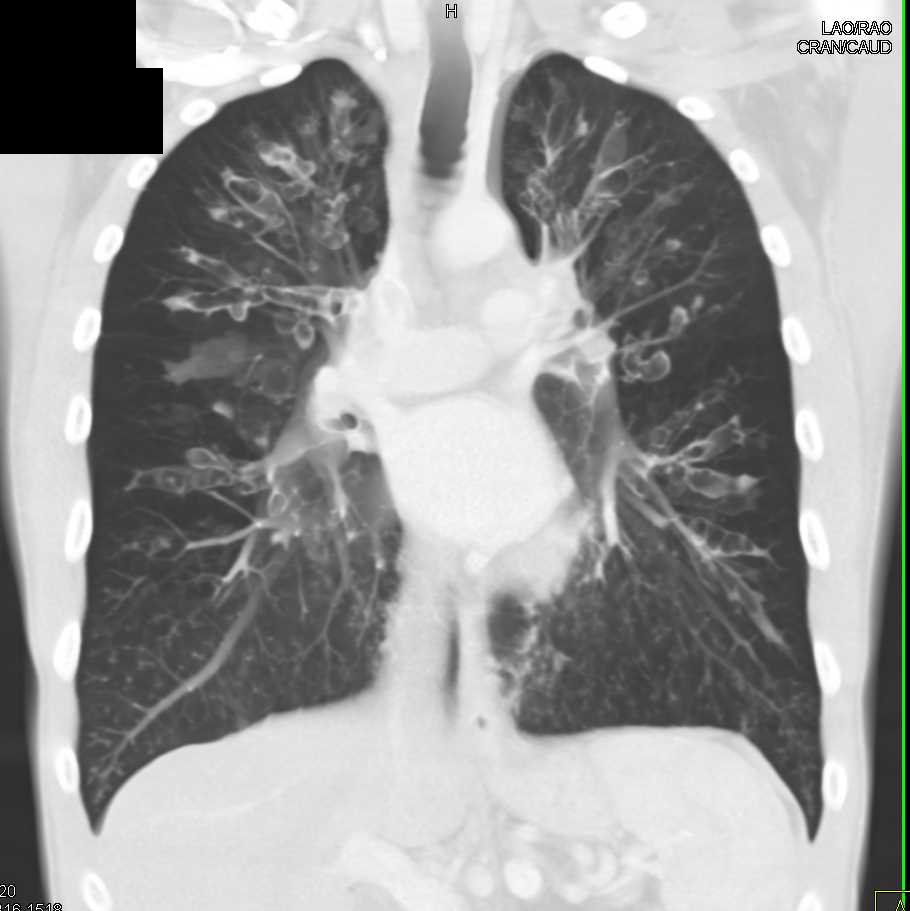

Chest CT scan areas of unilateral emphysema and cystic bronchiectasis Cystic Bronchiectasis Chest X Ray Cystic bronchiectasis where an airway is dilated into a rounded sphere is typically seen associated with cystic fibrosis (cf) and following tuberculous infection. It may be present on its own or may occur in combination. Chest ct scan if indicated (e.g., hemoptysis, or concern for pulmonary embolism). Patients with cystic fibrosis typically develop bronchiectasis. Cystic bronchiectasis is one of the. Cystic Bronchiectasis Chest X Ray.